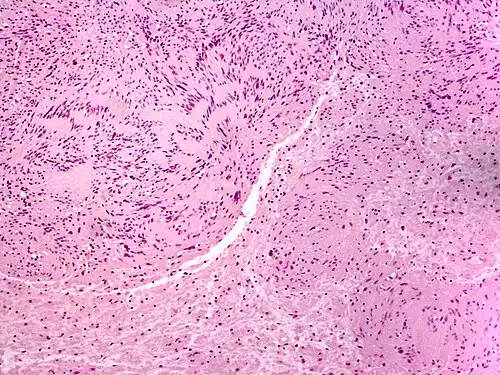

نوروم ( انگلیسی: Neuroma ) یا تومور عصبی، تومور و غدهٔ دردناکی است که بافت عصبی را فرامی گیرد. نوروم به توموری گفته می شود که از عصب منشأ گرفته یا عمدتاً از یاخته های عصبی و تارهای عصبی تشکیل شده است. نوروم نوعی بزرگ شدن پیازی شکل روی یک عصب متشکل از کلاف در هم پیچیده رشته های متداخل است.

نوروم یک رشد غیرطبیعی بافت عصبی ولی معمولاً رشد خوش خیم است، اما با ضخیم شدن بافت عصبی اغلب باعث درد شدید عصبی می شود.